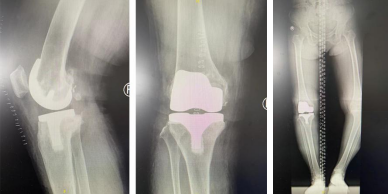

随后,郝亮、蒋涛、朱信飞手术团队为张大姐进行了智能导航下右侧人工全膝关节置换术。术中,在智能导航的规划下,精确定位力线位置,辅助手术医生进行截骨及假体安放,最终仅用时1.5小时便完成手术。经测量,患者下肢力线从术前的内翻25°、屈曲畸形10°,至术后内翻0°、膝伸直可达0°、膝关节屈曲至达120°,改善明显。

术后

相较传统手术来讲,以往人工关节置换手术往往要依赖主刀医生的经验,缺乏客观的测量工具,手术很难达到最佳效果,而在智能导航技术的支持下,力线的重建、假体的选择以及准确位置的置入,各项数据的精准化与精细化,是传统手术难以达到的。此外,使用智能导航技术可以使患者在术中出血少、术后痛苦小、恢复速度快!